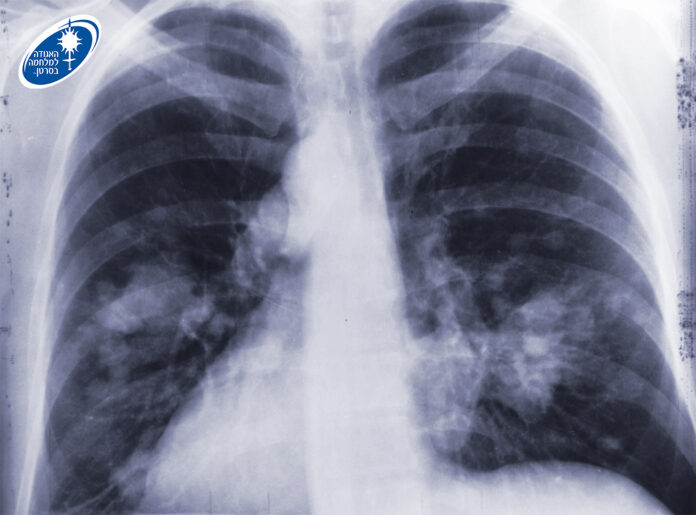

באגודה מעדכנים כי ניתן לגלות סרטן ריאה בשלב מוקדם ומציל חיים. כ-80% מהמקרים של סרטן זה קשורים בעישון, ולכן למעשנים כבדים בהווה או בעבר מומלץ לבצע מגיל 50, בדיקת CT במינון נמוך לגילוי מוקדם של סרטן הריאות. הבדיקה נכנסה לסל הבריאות ב-2025 לאנשים בני 75-64 עם היסטוריה של 20 שנות קופסה ומעלה, אם הם מעשנים בפועל או אם הפסיקו לעשן ב-15 השנים האחרונות.

מומחי האגודה למלחמה בסרטן מדגישים כי אם אחד מהתסמינים המפורטים לעיל נמשכים למעלה משלושה שבועות, חשוב להיבדק על ידי רופא משפחה. כל התסמינים עלולים להיגרם גם מעישון או ממחלות אחרות שאינן סרטן. לעיתים סרטן ריאה מאובחן באופן אקראי באנשים שאינם סובלים מתסמינים כלל, אך נבדקים בצילום או בסריקת ריאות לבירור בעיה אחרת.